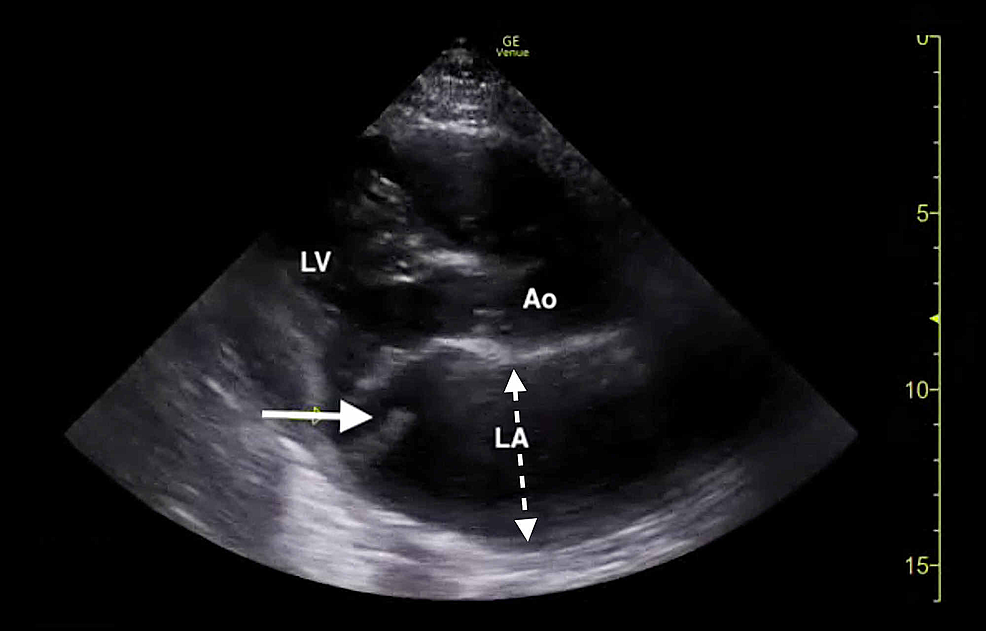

The clinical history was also concerning for an undiagnosed cardiomyopathy, particularly given the heart murmur appreciated on examination and his stated history of MVP for which the patient had never sought outpatient cardiology follow-up. Bedside LUS and FOCUS were then performed by emergency medicine resident physicians. LUS was notable for the presence of a diffuse B-line profile consistent with pulmonary edema (Figure 1). FOCUS was unremarkable for evidence of pericardial effusion, signs of right heart strain, or decreased LV contractility. However, FOCUS revealed a dilated left atrium (LA) and a suspected posterior FML, with the posterior MV leaflet seen protruding into the LA (Figures 2, 3; Videos 1, 2).

The constellation of FOCUS findings immediately prompted a formal comprehensive transthoracic echocardiogram (TTE) and emergent cardiology and cardiothoracic surgery consultations. TTE confirmed preserved LV systolic function, LA dilation, and flail motion of the posterior MV leaflet with severe eccentric MR (Figures 4, 5; Videos 3-5).